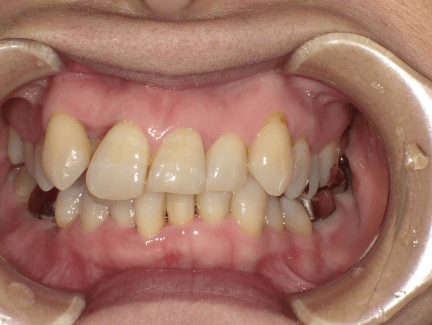

顎が小さくバランスが悪い状態

歯が大きくバランスが悪い状態